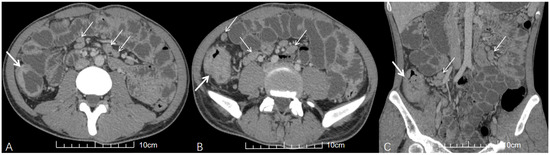

Clinical and CT Features of HIV-Negative and HIV-Positive Patients with Abdominal Tuberculous Lymphadenopathy

Background: The diagnosis of abdominal tuberculous lymphadenopathy (ATBL) remains challenging in clinical practice. Patients with ATBL and HIV infection may have atypical clinical and computed tomography (CT) features. The aim of this study was to investigate the impact of HIV infection on the clinical and CT features of ATBL patients. Methods: From January 2012 to March 2023, 178 patients with untreated ATBL were retrospectively analyzed. Patients with ATBL were classified into HIV-negative group (n = 152) and HIV-positive group (n = 26). In addition to the clinical characteristics of the patients, the features of ATBL (e.g., size and location) were evaluated via CT. The Mann–Whitney U test (for continuous variables) and Fisher’s exact test (for categorical variables) were used to compare clinical data and CT imaging features between the two groups. Missing values were handled using multiple imputation, and the Benjamini–Hochberg procedure was applied to control the false discovery rate (FDR) in multiple comparisons. Post hoc power analysis for key variables was performed. Results: Compared with the HIV-negative group, the HIV-positive group had older age, lower CD4+ T-cell counts, and larger ATBL diameter. The HIV-positive group also showed a stronger tendency for disease dissemination, with significantly higher rates of smear positivity, miliary pulmonary tuberculosis (PTB), and disseminated tuberculosis (TB). On CT imaging, the HIV-positive group had a higher frequency of ATBL involvement in the upper para-aortic region, portacaval space, and hepatogastric ligament. In contrast, abdominal distension was more common in the HIV-negative group. post hoc power analysis confirmed that most key variables had adequate statistical power (≥0.8), except for age (power = 0.597) and ATBL diameter (Power = 0.769). Conclusions: The clinical and CT features of ATBL differ significantly between HIV-negative and HIV-positive patients. Full article

Figure 1